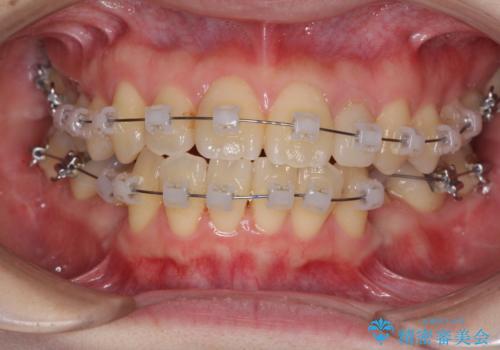

- 矯正装置

- クリアブラケット

- 治療期間

- 1年3ヶ月

- 治療回数

- 10-30回